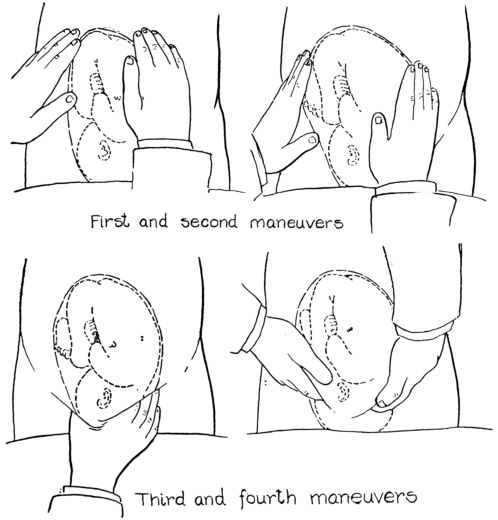

| 57. | First maneuver in abdominal palpation | 225 |

| 58. | Second maneuver in abdominal palpation | 226 |

| 59. | Third maneuver in abdominal palpation | 227 |

| 60. | Fourth maneuver in abdominal palpation | 228 |

| 61. | Diagrams showing positions of nurse’s hands in four maneuvers of abdominal palpation | 229 |